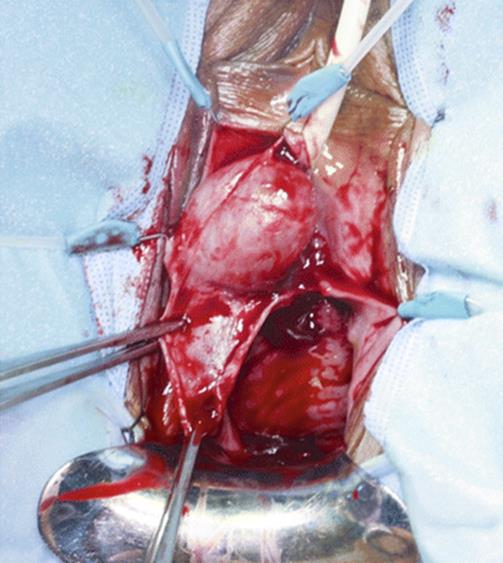

The patient in Figs. 8.35, 8.36, 8.37, 8.38, and 8.39 presented with vaginal discomfort, defecatory dysfunction, and a large, nontender mass of the posterior vaginal wall extending to the perineum.

Fig. 8.35

A coronal MRI shows the presence of a solid, well-circumscribed mass of the perineum (arrow)

Fig. 8.36

Exposure of the posterior vaginal wall and perineum shows a hard mass that extends from the posterior vaginal wall to the perineum. A perineal approach to remove the mass was performed. The arrowsoutline the lesion in the perineum